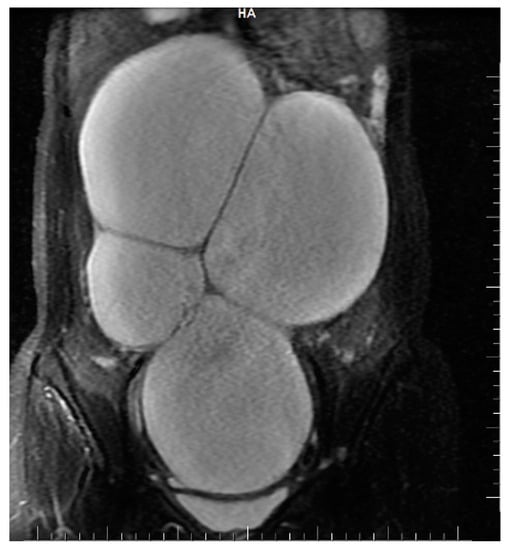

The abdomino-pelvic US showed a thin-walled, multilocular cystic mass occupying almost the entire abdomen and pelvis, with transonic content and multiple septa, some of them thick. None of the ovaries were visualized, and there was no free peritoneal fluid. Because the cyst origin could not be specified, we requested an abdomino-pelvic MRI, which showed a 115/224/350 mm cystic tumor originating in the right ovary that waswell-defined by a regular wall, multiloculated, had liquid content with some areas of high signal intensity in T1, and presented moderate mural and septal enhancement after gadolinium injection; the suggested diagnosis was ovarian cystadenoma (Figure 2 and Figure 3).

Figure 2. Coronal STIR sequence shows a well-defined voluminous, multiloculated, multiseptate cystic mass occupying the pelvis and the large peritoneal cavity.